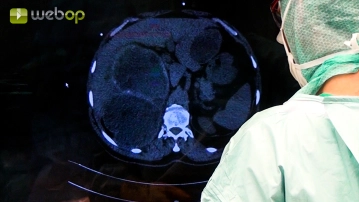

Coleta de achados; Adesiólise; Preparação do pericisto extra-hepático no lobo hepático esquerdo

Configurações de som Tipicamente, os cistos apresentam adesões maciças ao entorno. Inicialmente, as adesões do cisto do lado esquerdo ao omento são dissecadas. A abertura acidental dos cistos deve ser estritamente evitada. Então, torna-se aparente que o pericisto está aderido ao antro gástrico. Essas adesões agora são dissecadas com cuidado, às vezes usando pinças Overholt.

Uma vez que o pericisto que protrui sobre a superfície do fígado é dissecado livre, ele é inicialme